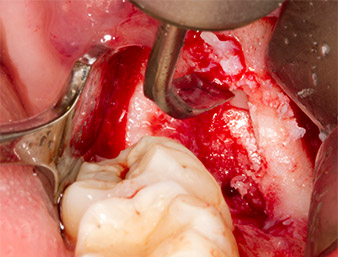

To obtain autogenous material for subsequent wound treatment, healthy bone chips were harvested from the surroundings of the root remnant with a piezo surgical instrument (Piezomed B5) (Fig. 5).

Piezomed B5

Fig. 5: Bone in the region of the alveole is lifted with a chisel-shaped piezo surgical instrument (Piezomed B5). This bone is used as autologous augmentation material after removal of the root remnant (cf. Fig. 13 and 14).

The autogenous tissue was removed with the scraper-shaped section of the working part of the instrument and stored in a physiological saline solution until further use (cf. Fig. 13).

To expose the root remnant with as little trauma as possible to the tissue, a further instrument was used (Piezomed S2) that is primarily indicated for preparing the lateral window in augmentations of the sinus floor. The diamond-coated ball was additionally used to smooth sharp bone edges (Fig. 6 and 7). All the Piezomed attachments were used with the relevant automatic default setting without booster function.

Piezomed S2

Fig. 6: The root remnant is carefully exposed with a diamond-coated spherical instrument (Piezomed S2), bone edges are smoothed.